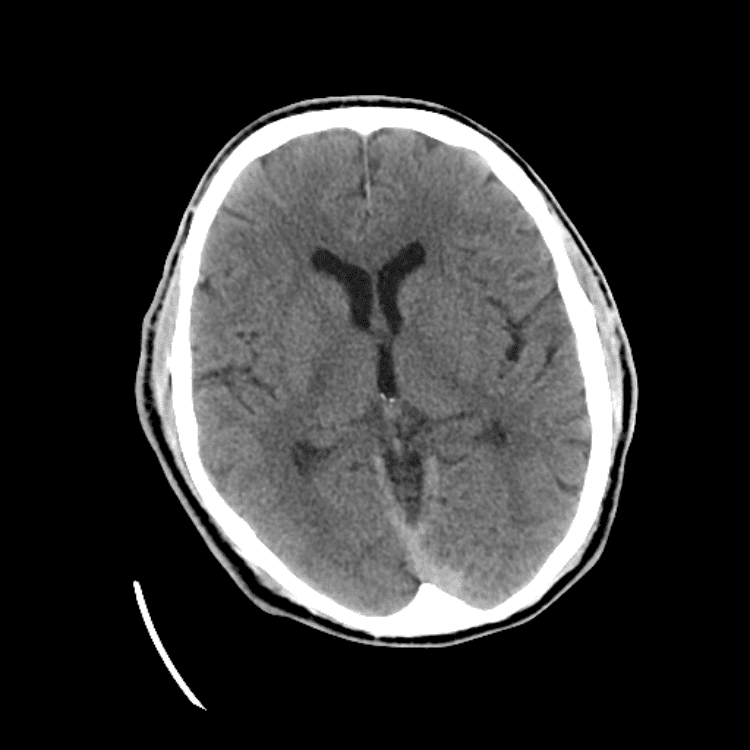

Nontraumatic Brain

Practice